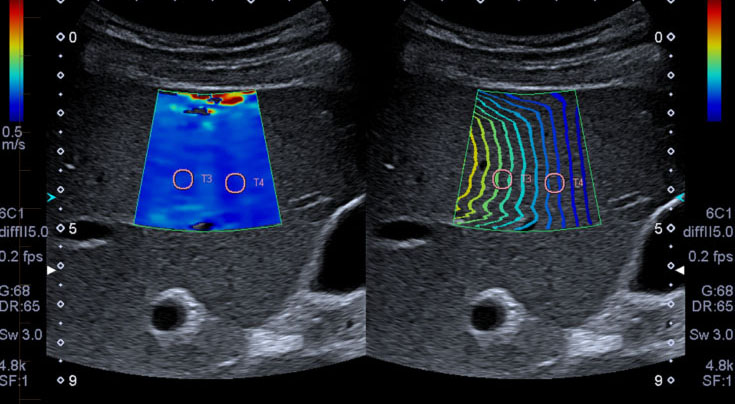

Identificarea elastografica a unui nodul ca fiind cancer reduce drastic numarul de intepaturi in prostata si disconfortul asociat.Imaginea prezentata indica doi noi noduli benigni in partea centrala a prostatei.